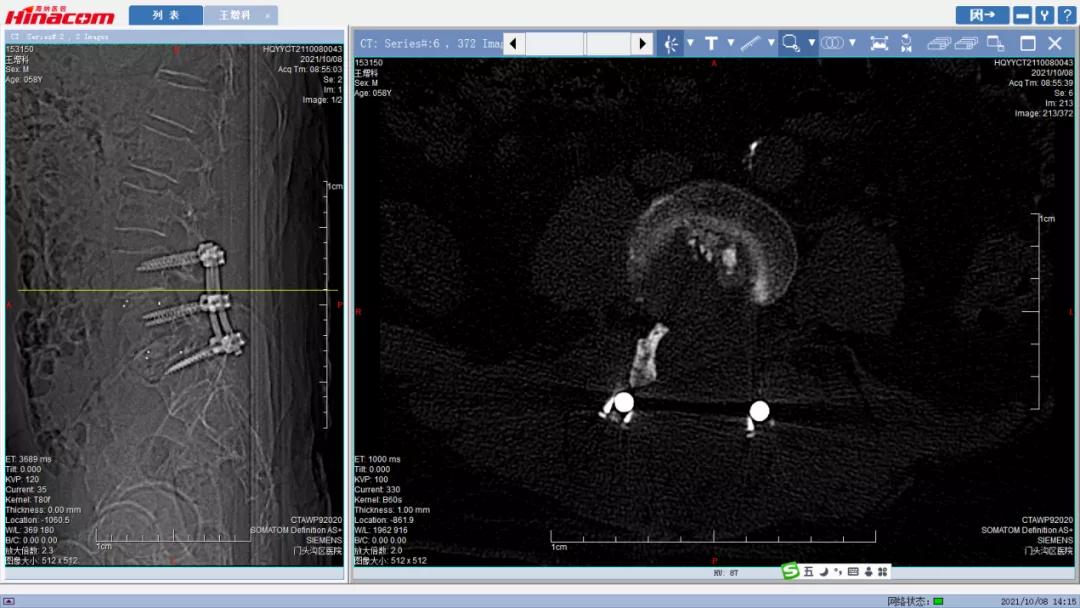

腰34椎间盘--术前CT

腰45椎间盘--术前CT